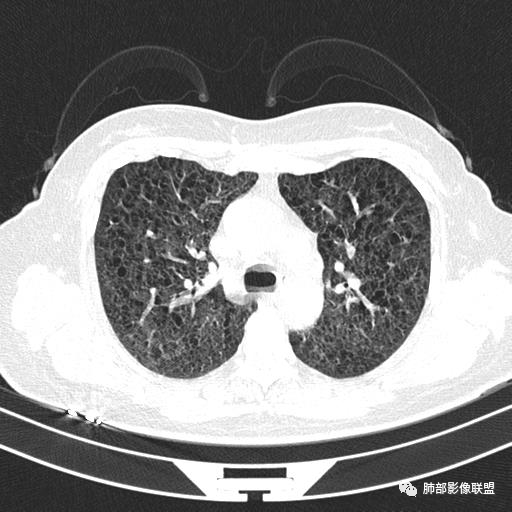

双肺弥漫囊腔,累及肋膈角,囊腔形态相对规则单一。

CT平扫示双肺弥漫分布大小不等囊状薄壁透光区,无内、中、外带分布差异,间质稍示增厚。拟LAM

中年女性育龄期妇女,咳嗽气喘,无吸烟史,有苯吸入史。影像:双肺弥漫均匀小囊腔,无明显分布优势,囊腔形态欠规则,壁薄,部分囊腔边缘血管征,伴双肺弥漫磨玻璃影,无结节,考虑lam,鉴别苯中毒肺损伤,囊腔多有分布优势,小叶中心分布为主,形态规整等

女,46,活动性气喘1年。苯吸入史半年。胸部CT:两肺弥漫囊腔,上至肺尖,下至肋膈角,形态类似小囊腔。考虑:LAM,鉴别LIP,BHD,PLCH等。

双肺弥漫大小不一薄壁含气囊腔,囊间肺组织正常,正常肺背景,肺尖肺底受累;青年女性,气喘,支持LAM

双肺多发大小相近的囊状影,分布趋势趋于一致,中年女性,考虑LAM。部分囊内见血管及分隔影,小叶中心性肺气肿代排

CT表现:双肺弥漫大小不等的薄壁囊腔,囊壁<2mm,外形规则,血管影多位于囊腔周围,囊腔之间肺组织正常,随着疾病进展到晚期,囊腔变大、增多,不可胜数,囊腔可融合成较大的囊,与肺气肿相似,形成间质性肺纤维化。部分病例可出现结节影。